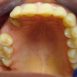

Interdisciplinary Treatment of Patients with Deep Overbite and Parafunctional Activity

Bruxism is defined as parafunctional grinding of teeth and due to the excessive wear of the posterior teeth, patients with long-standing bruxism often have pathological deep overbite. For many decades, treatment of bruxism and deep overbite was focused on reshaping the bite for achieving an occlusion free of deviations. Despite large efforts, the management of bruxism and subsequent deepening overbite was not obtained.